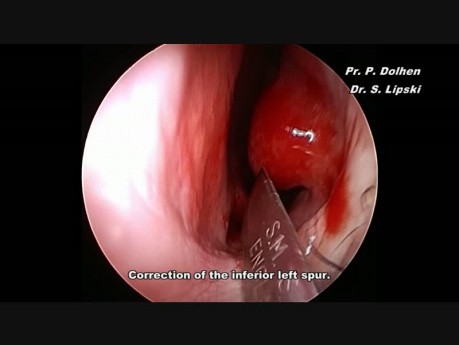

Edoskopowa septoplastyka: niewielka ostroga

Nagranie przedstawia endoskopową septoplastykę - usunięcie ostrogi przegrody nosowej po stronie lewej